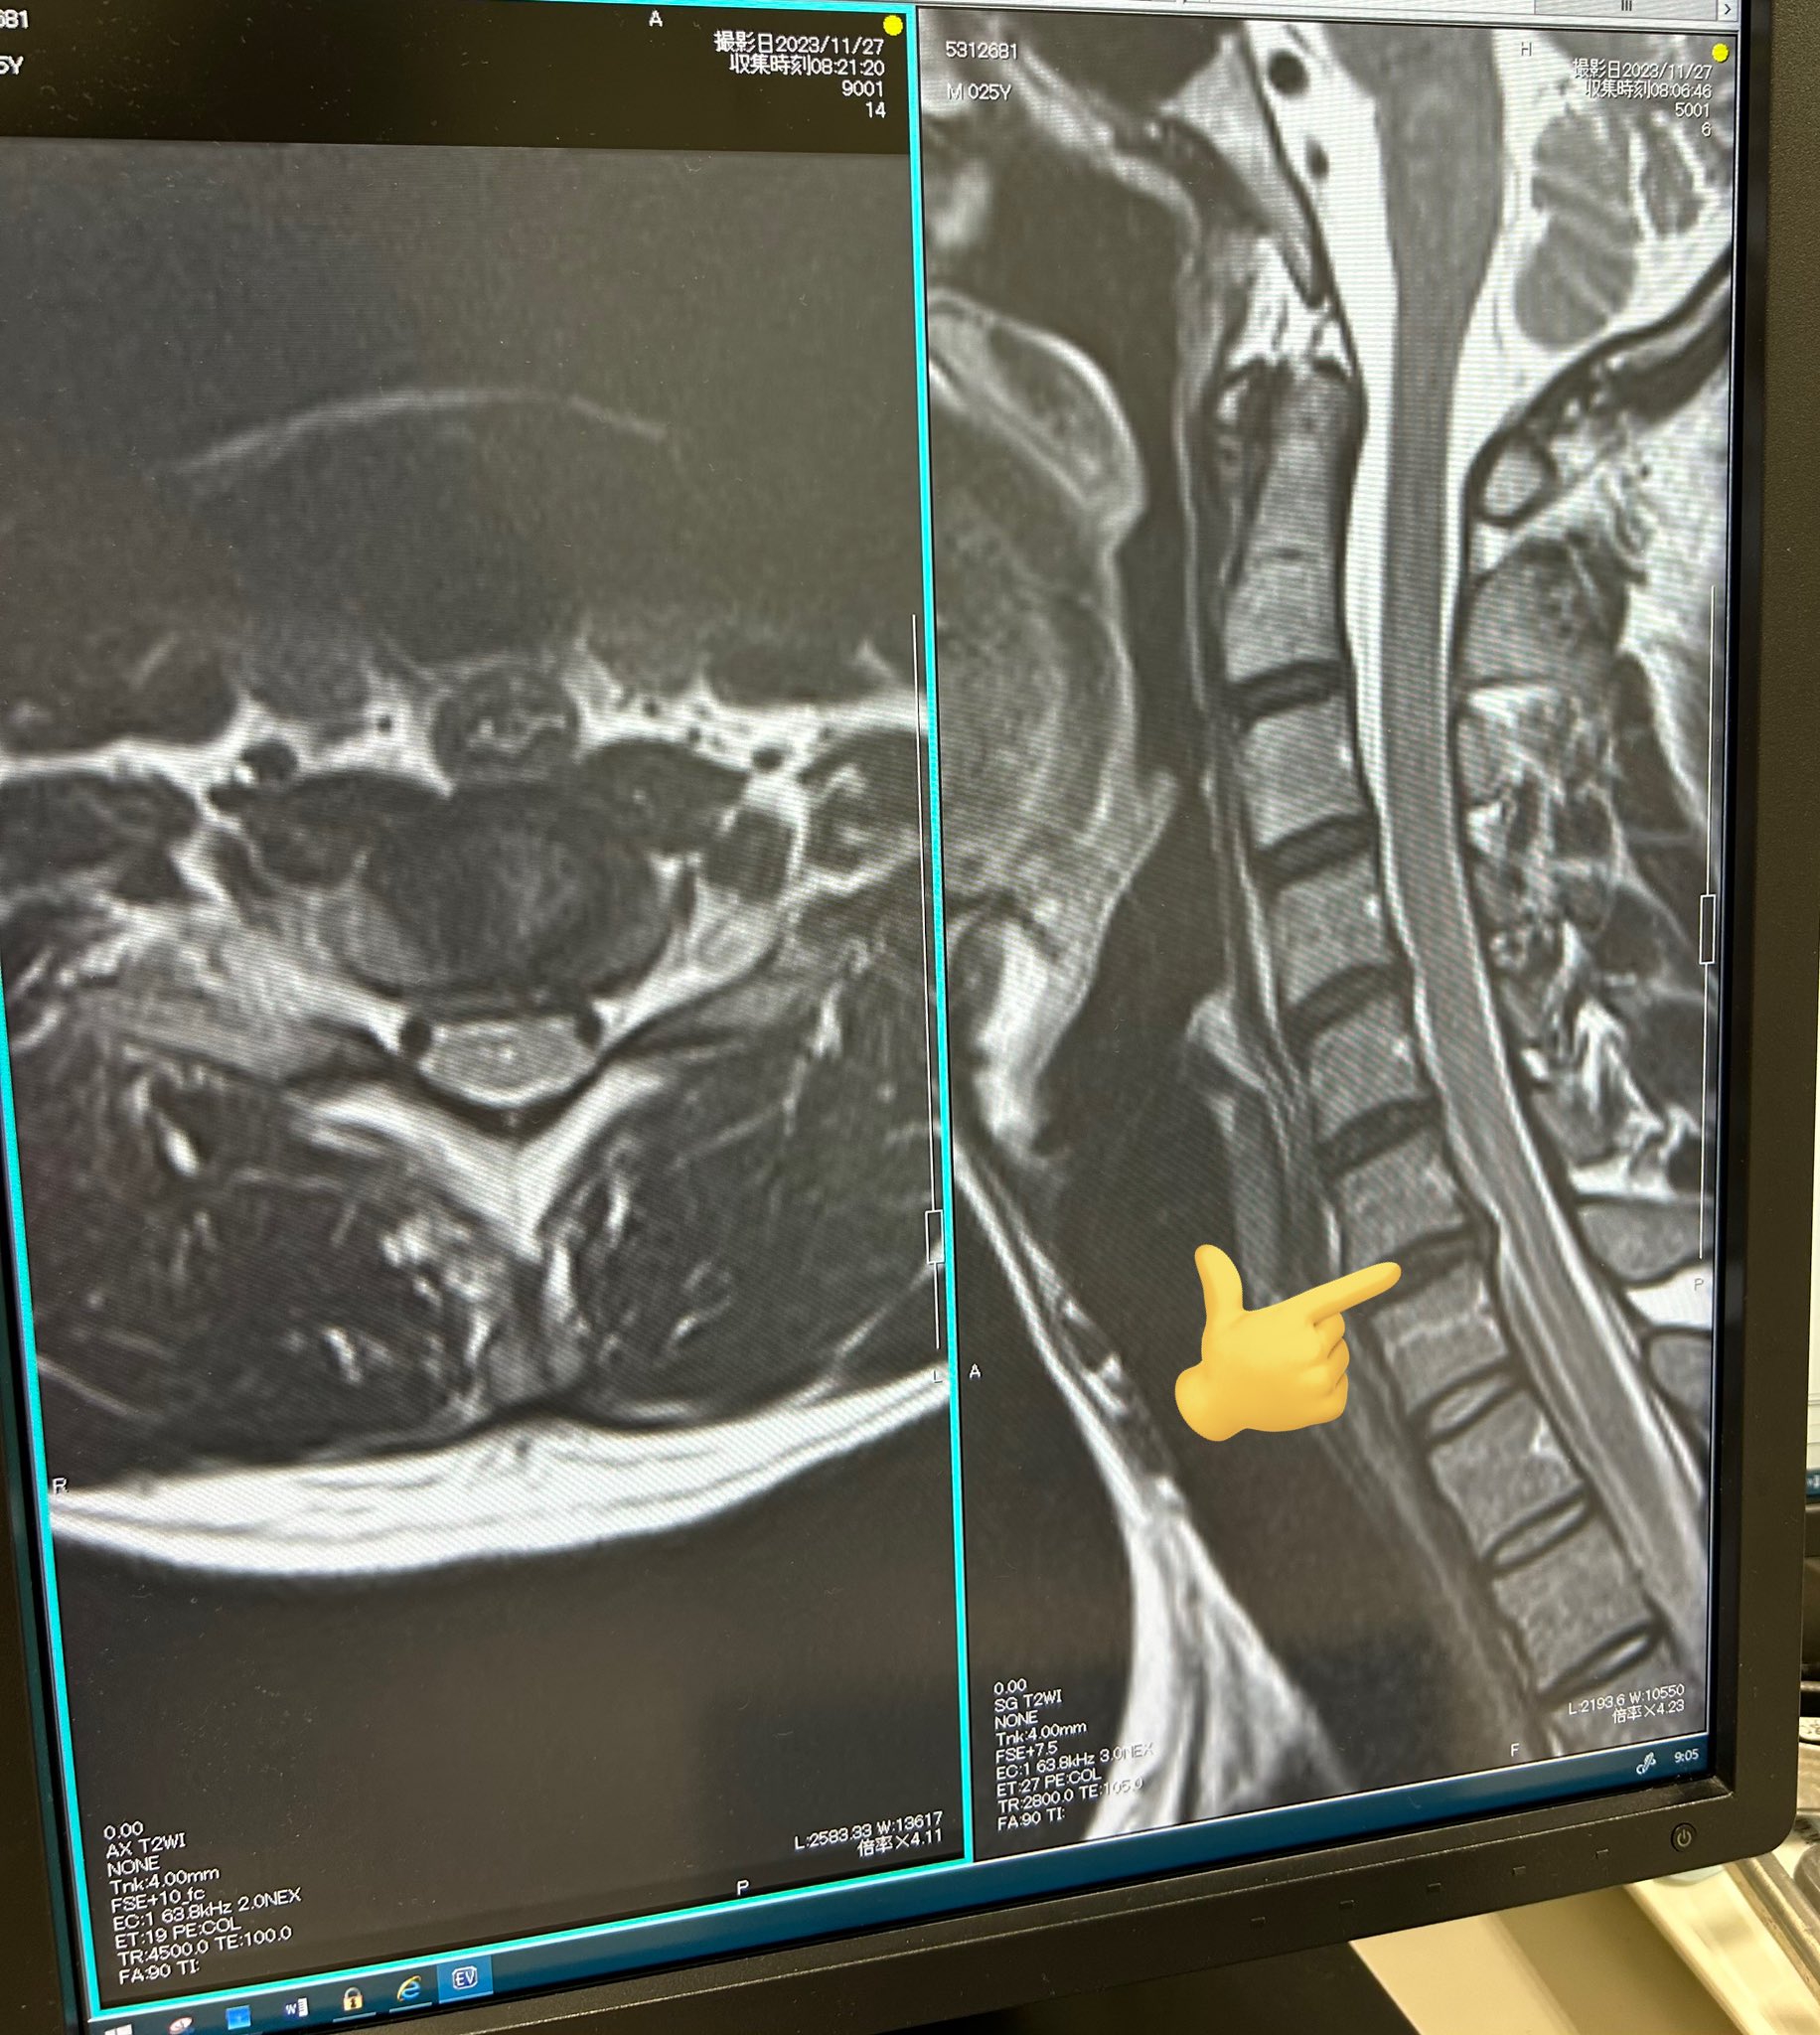

少し前の話になりますがこの度『頸椎椎間板ヘルニア』を発症しました。

(指で示してる少し突出してる所がヘルニア)

なんかずっと首と肩周り痛いなと思って病院でMRI撮ったらこれですわ。

まだ小さいヘルニアだからずっと同じ体勢でいたり激しい運動をしなければ悪化はしないらしですが、お絵描きマンには難しい話。